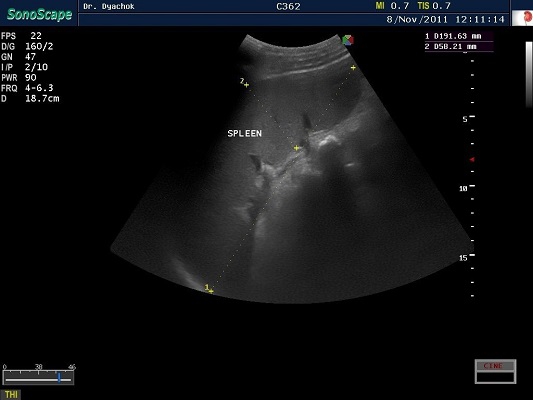

SonoScape S2N Vet – уникальная узи-система, выполненная в виде портативного ноутбука для легкой переноски. Отличается эта система цветным форматом визуализации, а также крайне чувствительными доплеровскими режимами, работающими на уровне премиальных аппаратов. При оптимальной цене – это очень хорошее и сбалансированное решение для ветеринарной клиники.

Диагональ монитора составляет 15,6 дюймов, что обеспечит комфортную работу для врачей и полный спектр визуализации для пациентов. Компактный вес не превышает 5 кг. (вместе с батареей), что оценят выездные бригады скорой помощи или ветеринары, выезжающие на дом.

Цифровая рабочая станция S2N Vet предполагает наличие жесткого диска для записи данных, составление и экспорт отчетов с возможностью добавления изображений, ведение базы данных пациентов.

Режимы сканирования SonoScape S2N Vet:

• В, М, В/М, В/В, 4В, Тканевая гармоника;

• Изменение масштаба изображения в режимах реального времени и стоп-кадра;

• Цветной, энергетический, направленный энергетический, импульсно-волновой,

• Постоянно-волновой допплер;

• Дуплексный, триплексный режимы;

• Трапецеидальное сканирование на линейных датчиках;

• Режим панорамного сканирования;

• Технология подавления спекл-шума MicroScan.